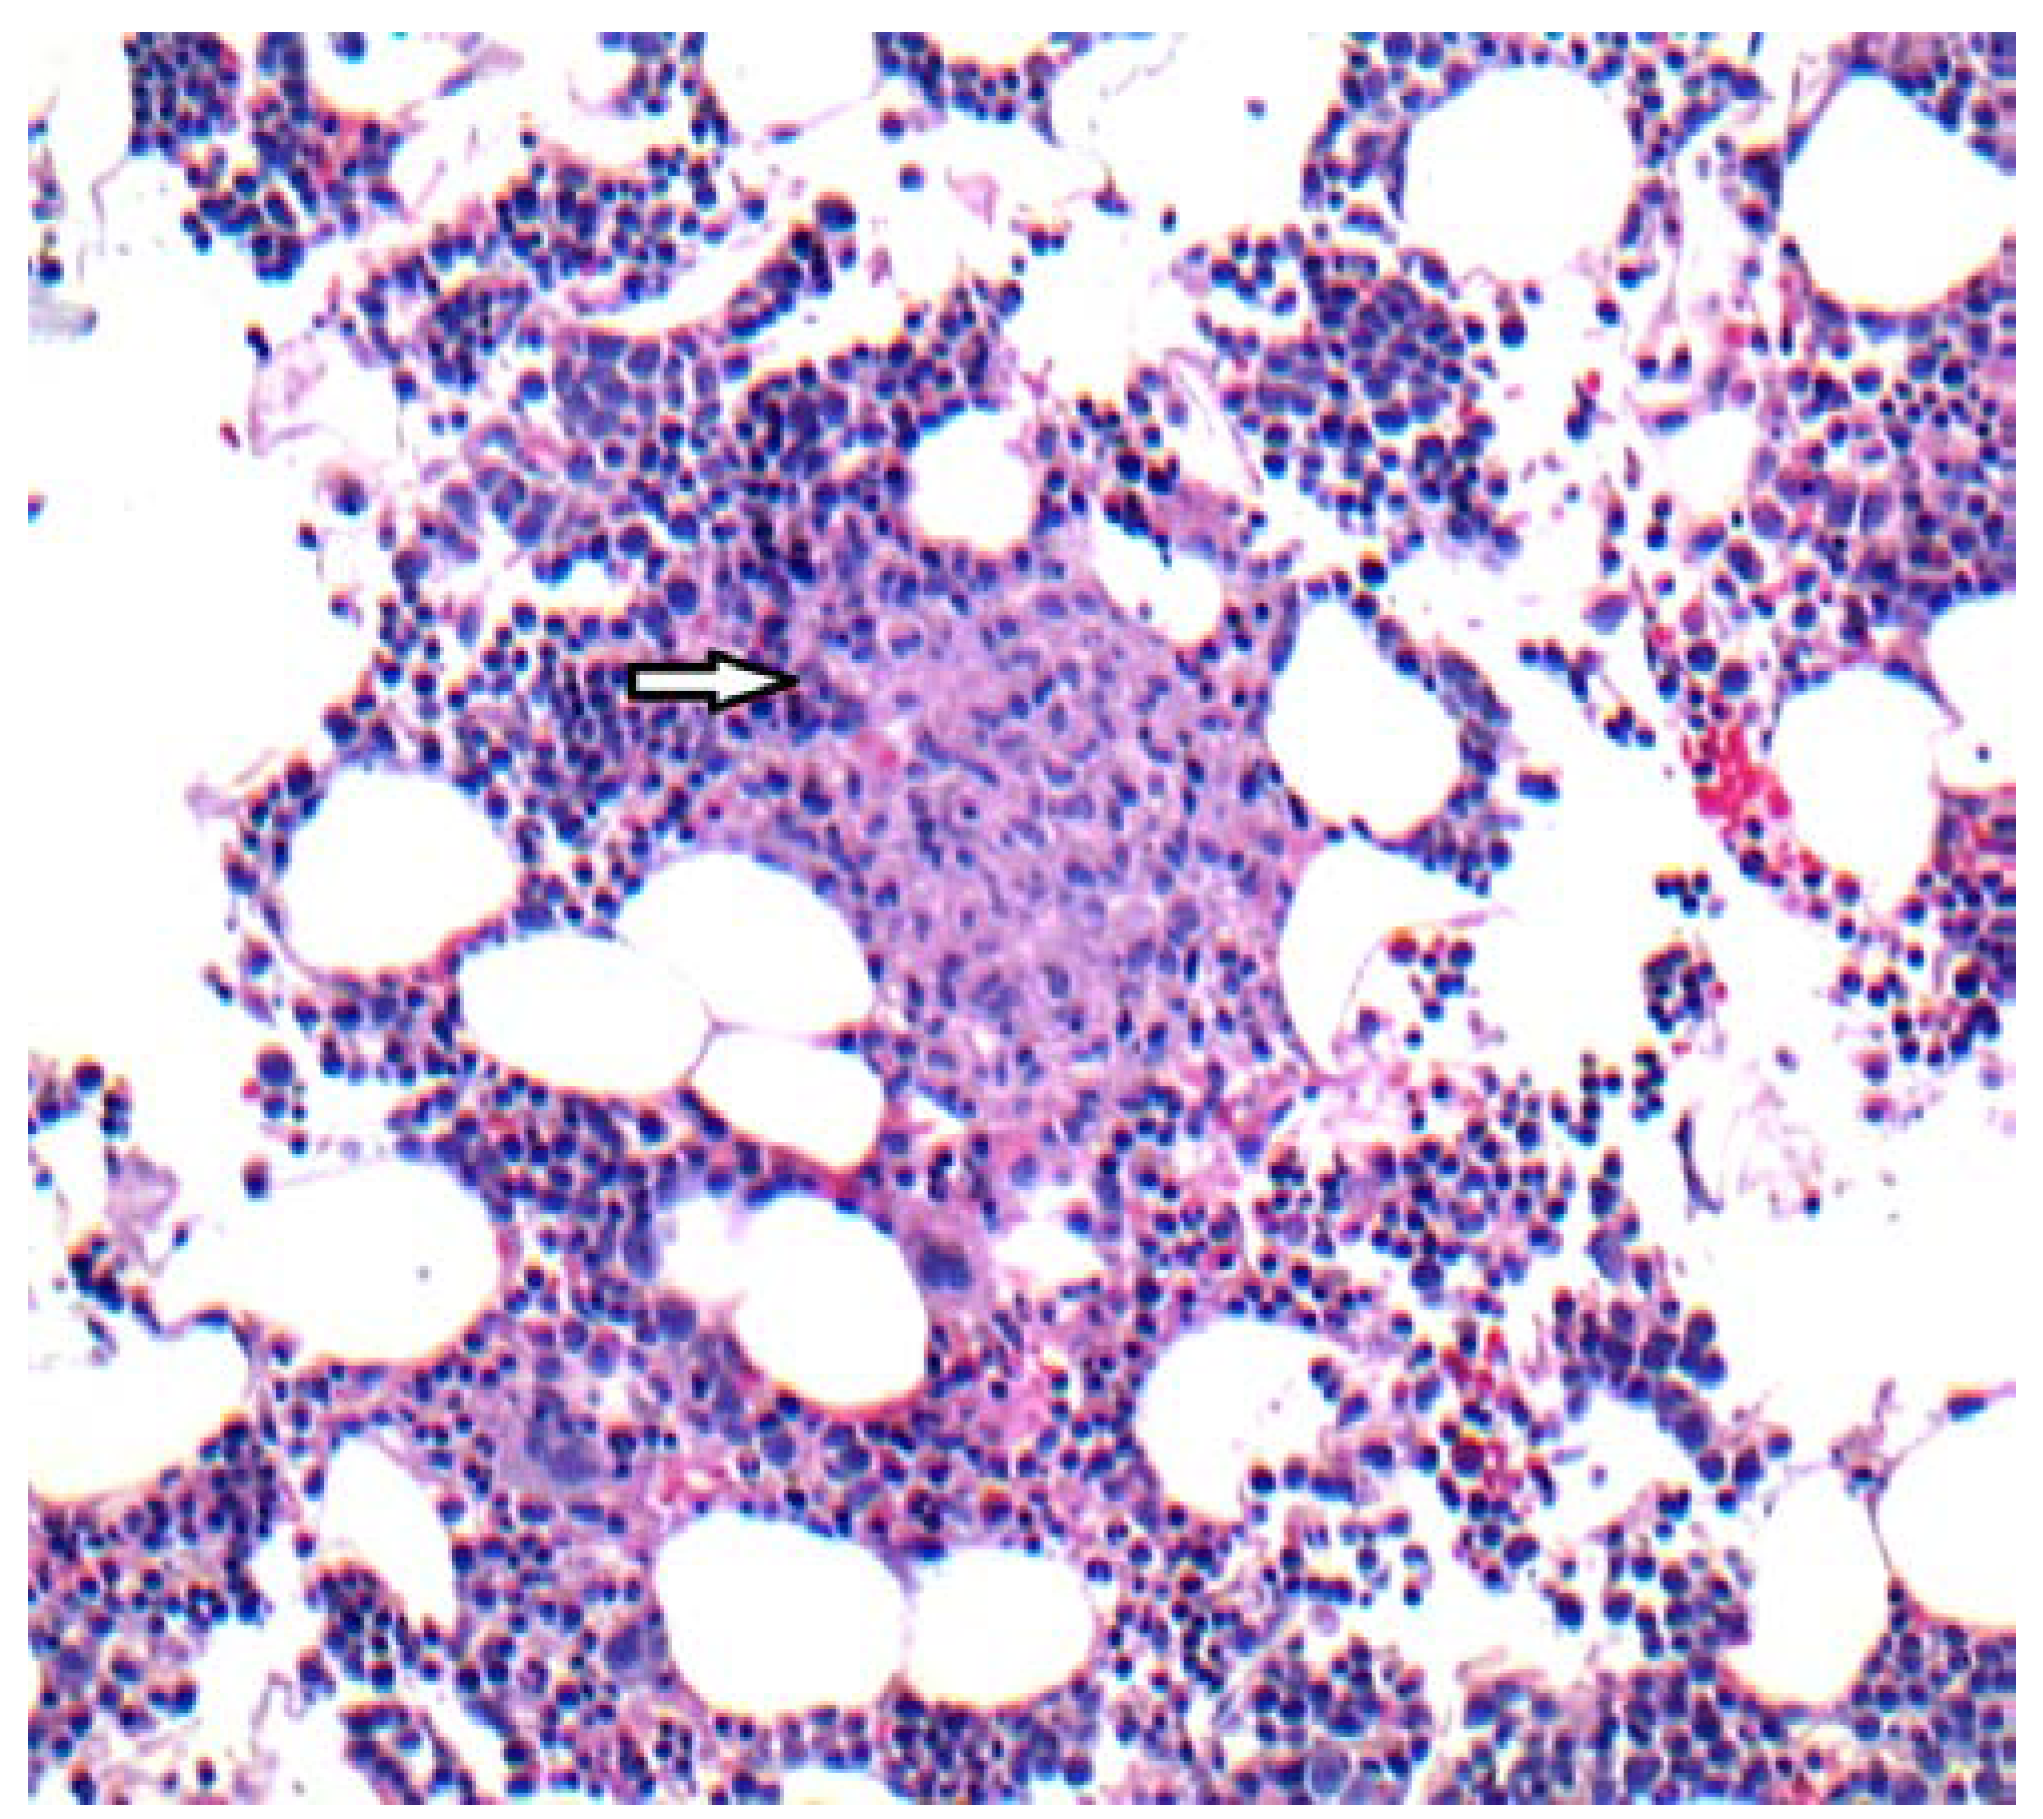

Case report